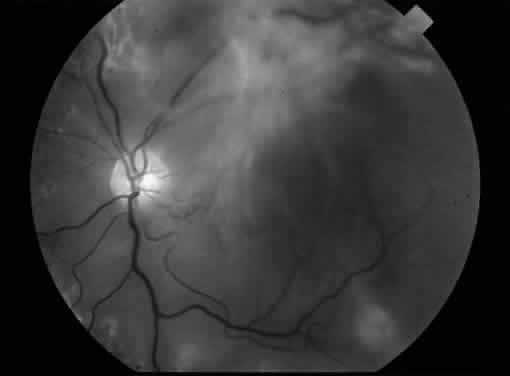

Fig. 6. A. Fundus photograph of an eye with vitreomacular traction syndrome. B. Fluorescein angiography showing deep, diffuse dye leakage.

Although the ETDRS showed that focal macular photocoagulation is beneficial in the treatment of clinically significant diabetic macular edema, it has been observed that some patients with diabetic macular edema and a taut, thickened posterior hyaloid do not respond to macular photocoagulation. It has been hypothesized that vitreous traction may cause or exacerbate macular edema in these patients. Lewis and coauthors report the results of pars plana vitrectomy with separation of the posterior hyaloid in 10 eyes with diabetic macular edema and traction associated with a thickened and taut premacular posterior hyaloid.24 Preoperative fluorescein angiography showed a deep, diffuse pattern of leakage in the macula (Fig. 6). Nine of 10 eyes had previous macular photocoagulation, and only 1 of these eyes responded with a temporary decrease in macular edema. Postoperatively, vision improved in nine eyes, and macular edema resolved in eight eyes. Postoperative complications included vitreous hemorrhage, rhegmatogenous retinal detachment, cataract formation, and mild epimacular membrane (each occurring in one eye). Other studies also report visual improvement after vitrectomy and posterior hyaloid separation in such patients.25 Tachi and Ogino report the results of pars plana vitrectomy with separation of the posterior hyaloid in 58 eyes with diffuse diabetic macular edema without posterior vitreous detachment.26 These patients differed from those in prior reports in that they did not manifest a taut, thickened posterior hyaloid, and thus it is not clear whether the posterior hyaloid was responsible for the macular edema. Although these patients showed an improvement in macular edema and visual acuity, this study was not controlled and included only a few patients. Thus, it is reasonable to consider vitrectomy and posterior hyaloid separation in patients with diffuse diabetic macular edema associated with a taut and thickened posterior hyaloid, whereas the long-term efficacy of such surgery in patients with diabetic macular edema without vitreoretinal interface abnormalities has not been conclusively proven.